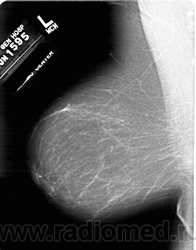

Жирная (не плотная) грудь

Умеренно плотная грудь

Плотная грудь

Маммограммы представляют собой изображения структур, проецируемых на плоскость: плотная грудная маммограмма, следовательно, состоит из многих других структур, которые необходимо проанализировать, чем более жирная, пустая грудь. По этой причине диагностировать рак молочной железы труднее для моложе, чем для пожилых женщин.

Нажмите на миниатюрные картинки, чтобы получить увеличенный размер.